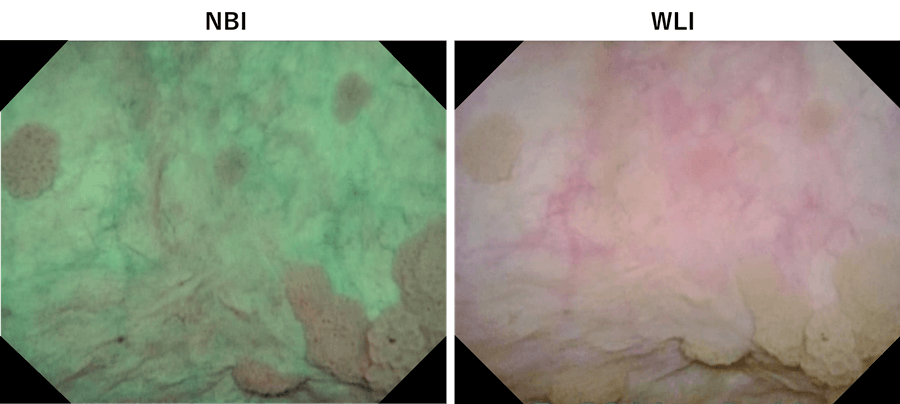

For TURBT, we mark the outside edge of the tumor before resection to identify the minimum area for resection. NBI helps determine the area for resection by clearly showing the tumor margins.

When viewing a tumor with associated lesions by WLI, lesions at the edge of tumor may be overlooked. After marking the tumor margins with WLI, switching to NBI sometimes allows us to find suspicious lesions outside the demarcated area. (Fig. 5, top). Therefore, we mark the area for resection under NBI observation before resection (Fig. 5, bottom).

Fig. 5. Top: White area observed with NBI is the margin marked under WLI observation. It is obvious that the papillary tumor extends outside the marked area. Bottom: Marking the edge of the tumor for the abnormal lesion identified with NBI. The area looks wider than the actual tumor when seen with WLI.